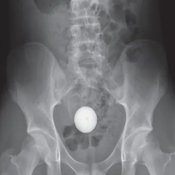

อย่างไรก็ดี ผลเอ็กซ์เรย์พบว่าลูกกอล์ฟติดอยู่ในลำไส้ใหญ่ส่วนซิกมอยด์ (sigmoid) ทำให้การเอาออกเป็นเรื่องท้าทายสำหรับแพทย์ ขั้นตอนในการดึงลูกกอล์ฟออกมาใช้เวลาสองชั่วโมงภายใต้การดมยาสลบ แม้จะพยายามหลายถึง 6 วิธี ได้แก่ ตาข่ายทางการแพทย์ สายสวน เครื่องดูดเสมหะ สายสวนบอลลูน ฯลฯ แต่วิธีทั้งหมดนั้นก็ไม่ช่วยให้ประสบความสำเร็จ